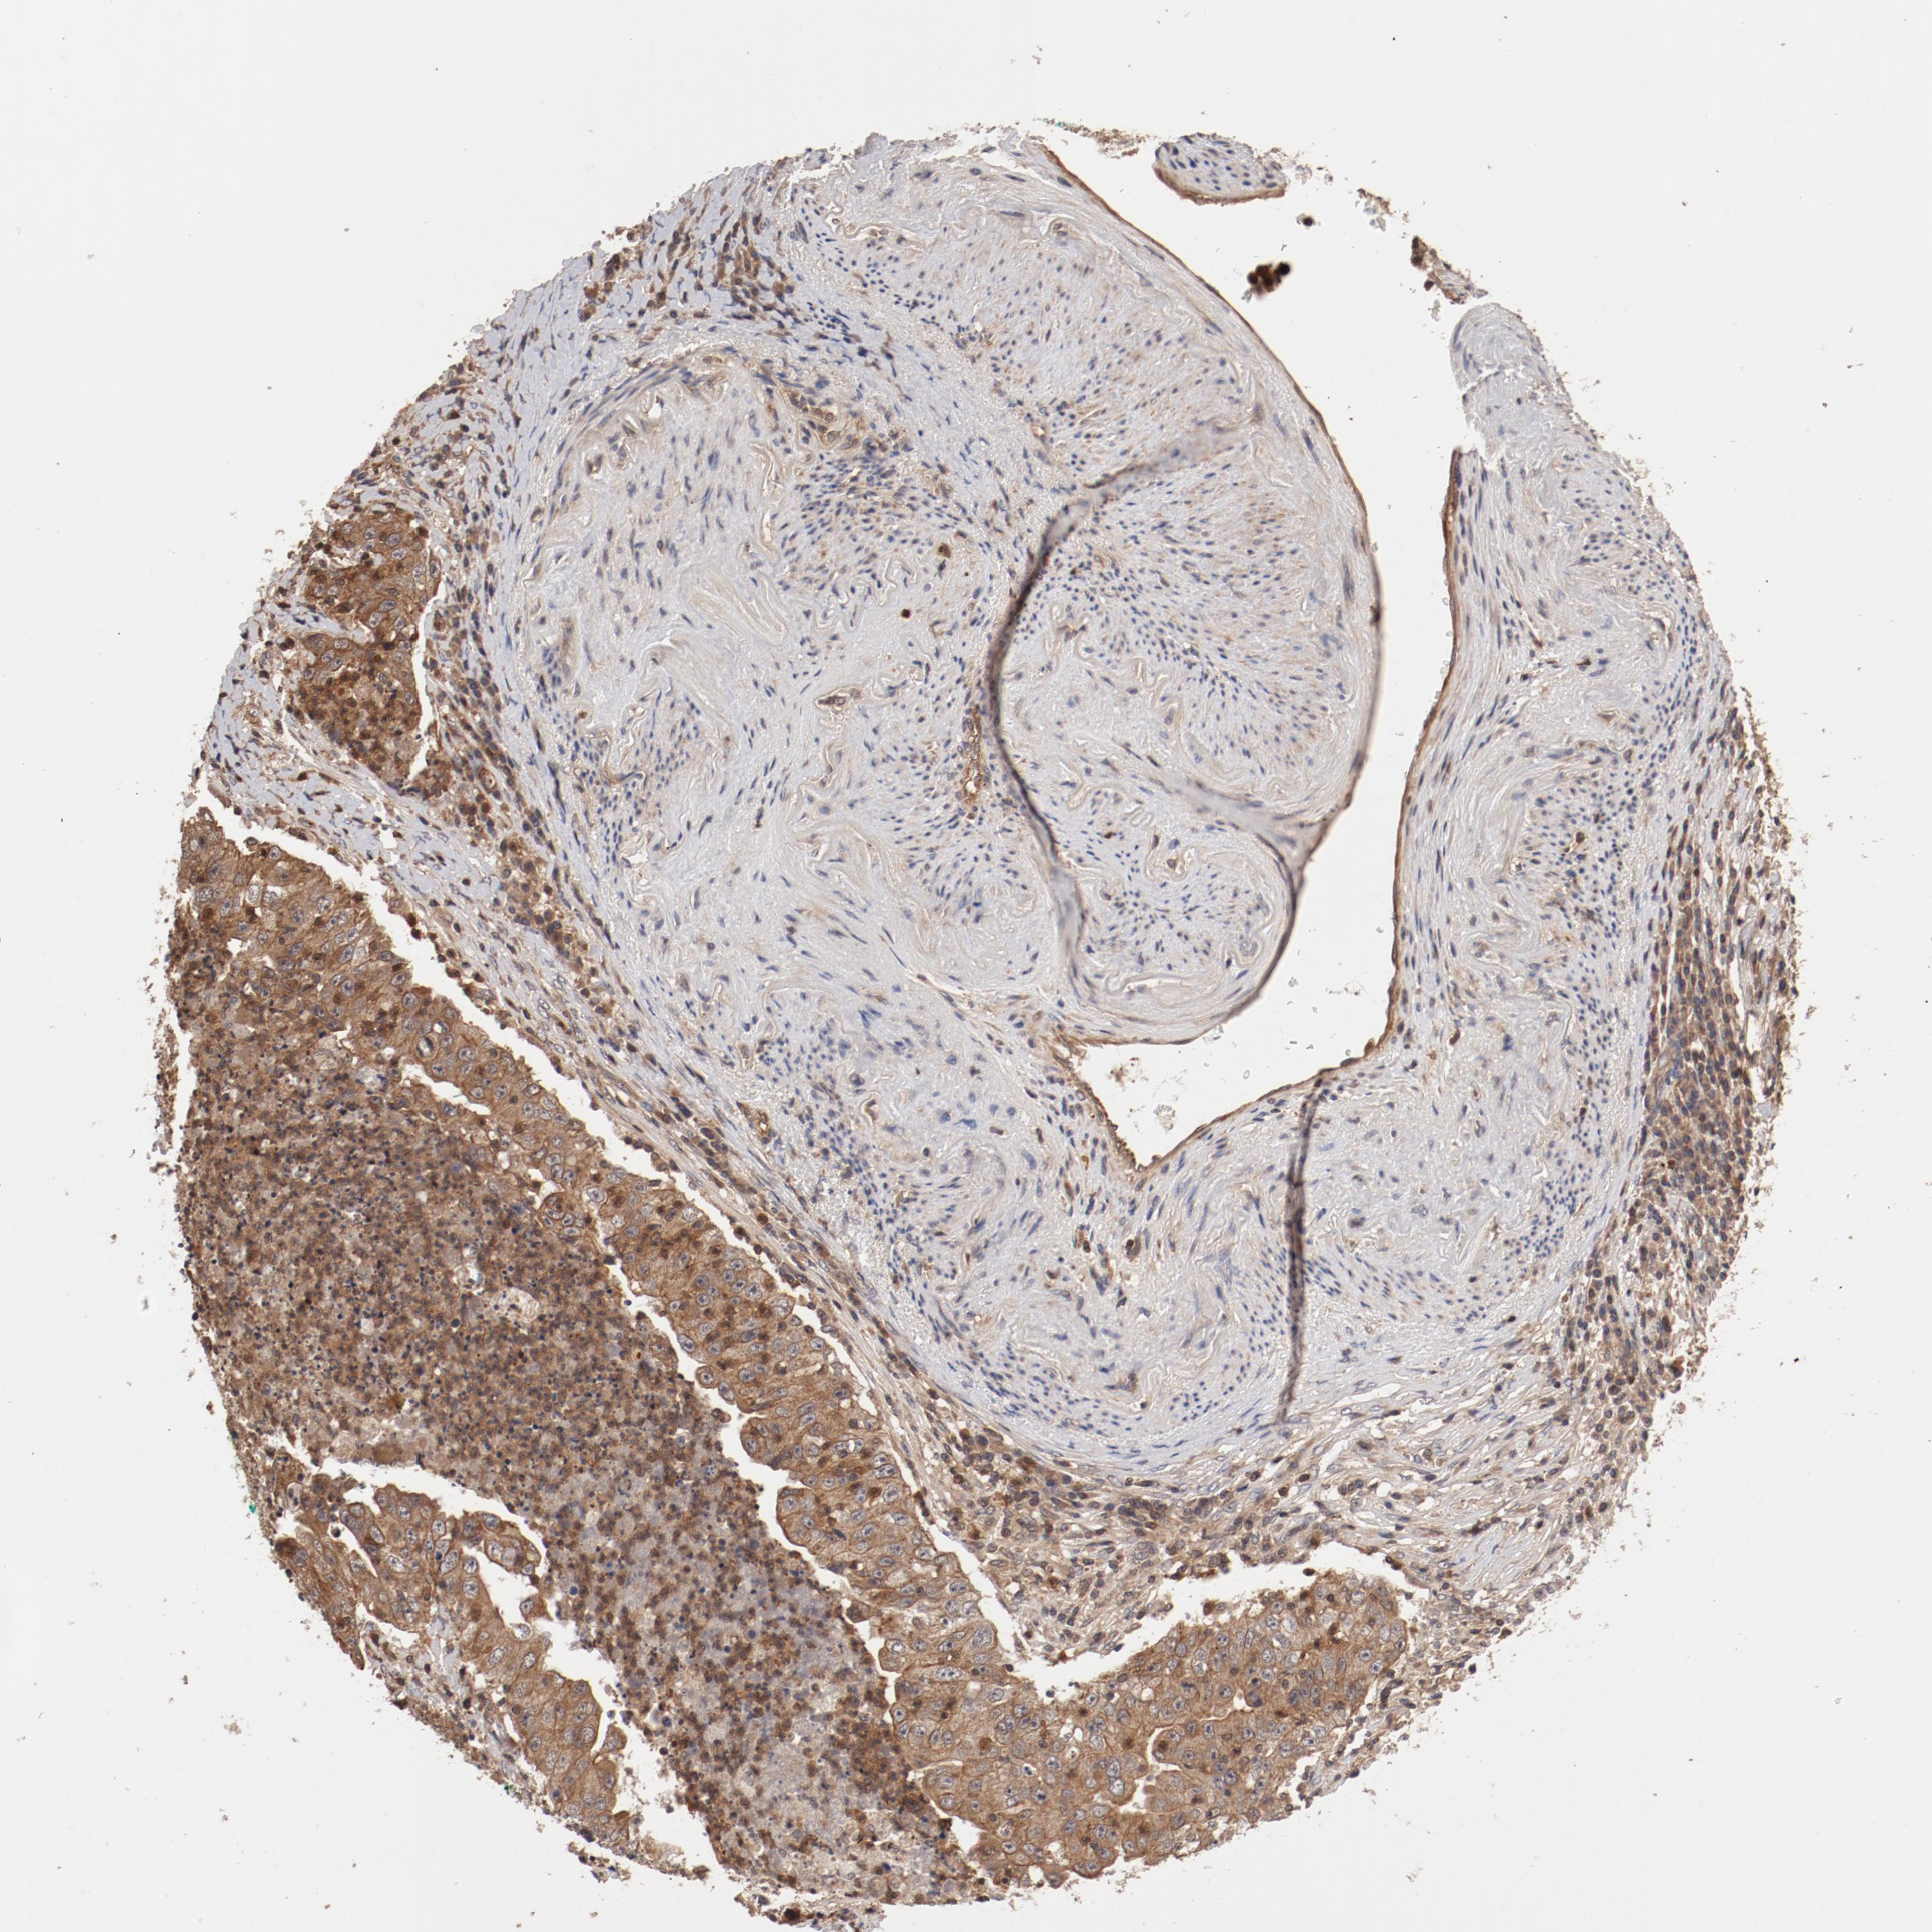

CANCER LUNG CANCER Show tissue menu

LUNG ADENOCARCINOMA (VALIDATION) - Interactive survival scatter ploti

GUF1 is not prognostic in Lung Adenocarcinoma (validation)

Average pTPM 7.4

Number of samples 105

LUNG SQUAMOUS CELL CARCINOMA (TCGA) - Interactive survival scatter ploti

GUF1 is not prognostic in Lung Squamous Cell Carcinoma (TCGA)

Average pTPM 3.9

Number of samples 489